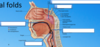

Black lines and blue lines pointing to?

Tonsils and blue lines?

What are valleculae?

Clinical significance?

Valleculae is the recess before the epiglottis. The spot where the laryngoscope goes for intubation. It is also where bits of food get stuck and make you feel like you are going to choke.

Seat the laryngoscope in the valicular (key landmark): posterior to that is the epiglottis which is where you will chuck a tube down into the trachea.

Laterally and posterior to the epiglottis is the __________.

Piriform fossa.

What is each of the arrows pointing to?

Including the green arrows?